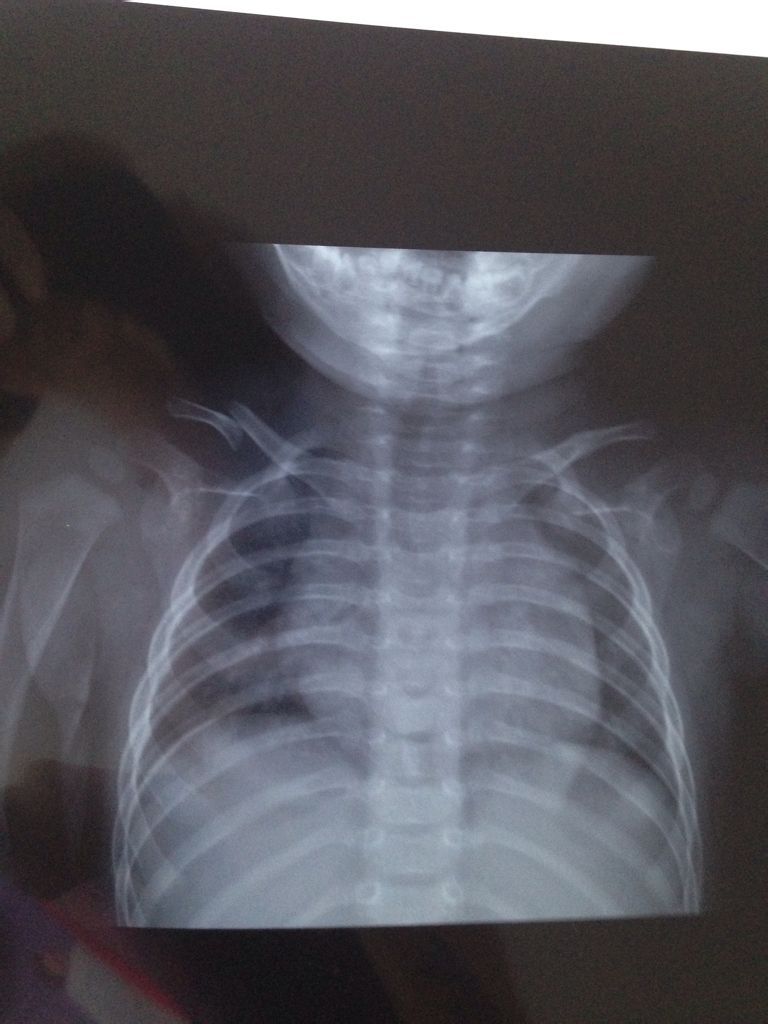

宝宝7个月锁骨骨折了,大夫说不用绷带固定,让自然生长,会有什么影响吗?需要注意什么? 点击展开 匿名用户 2015-08-28 20:02 为您推荐: 其他回答 你好,从你的片子看,这样长了恐怕张不好,可能会有畸形的。骨折错位很明显。长会长上,但是可能遗留畸形 hzwa1 2015-08-28 20:08 相关问题 三岁宝宝右侧锁骨骨折要多久能好,现在第九天,大夫只是用毛巾垫下手用绷带吊着,请问要多久能好会不会有 我锁骨骨折一个星期了 带绷带吃药的保守治 病情描述(发病时间、主要症状等):锁骨骨折八字绷带补钙